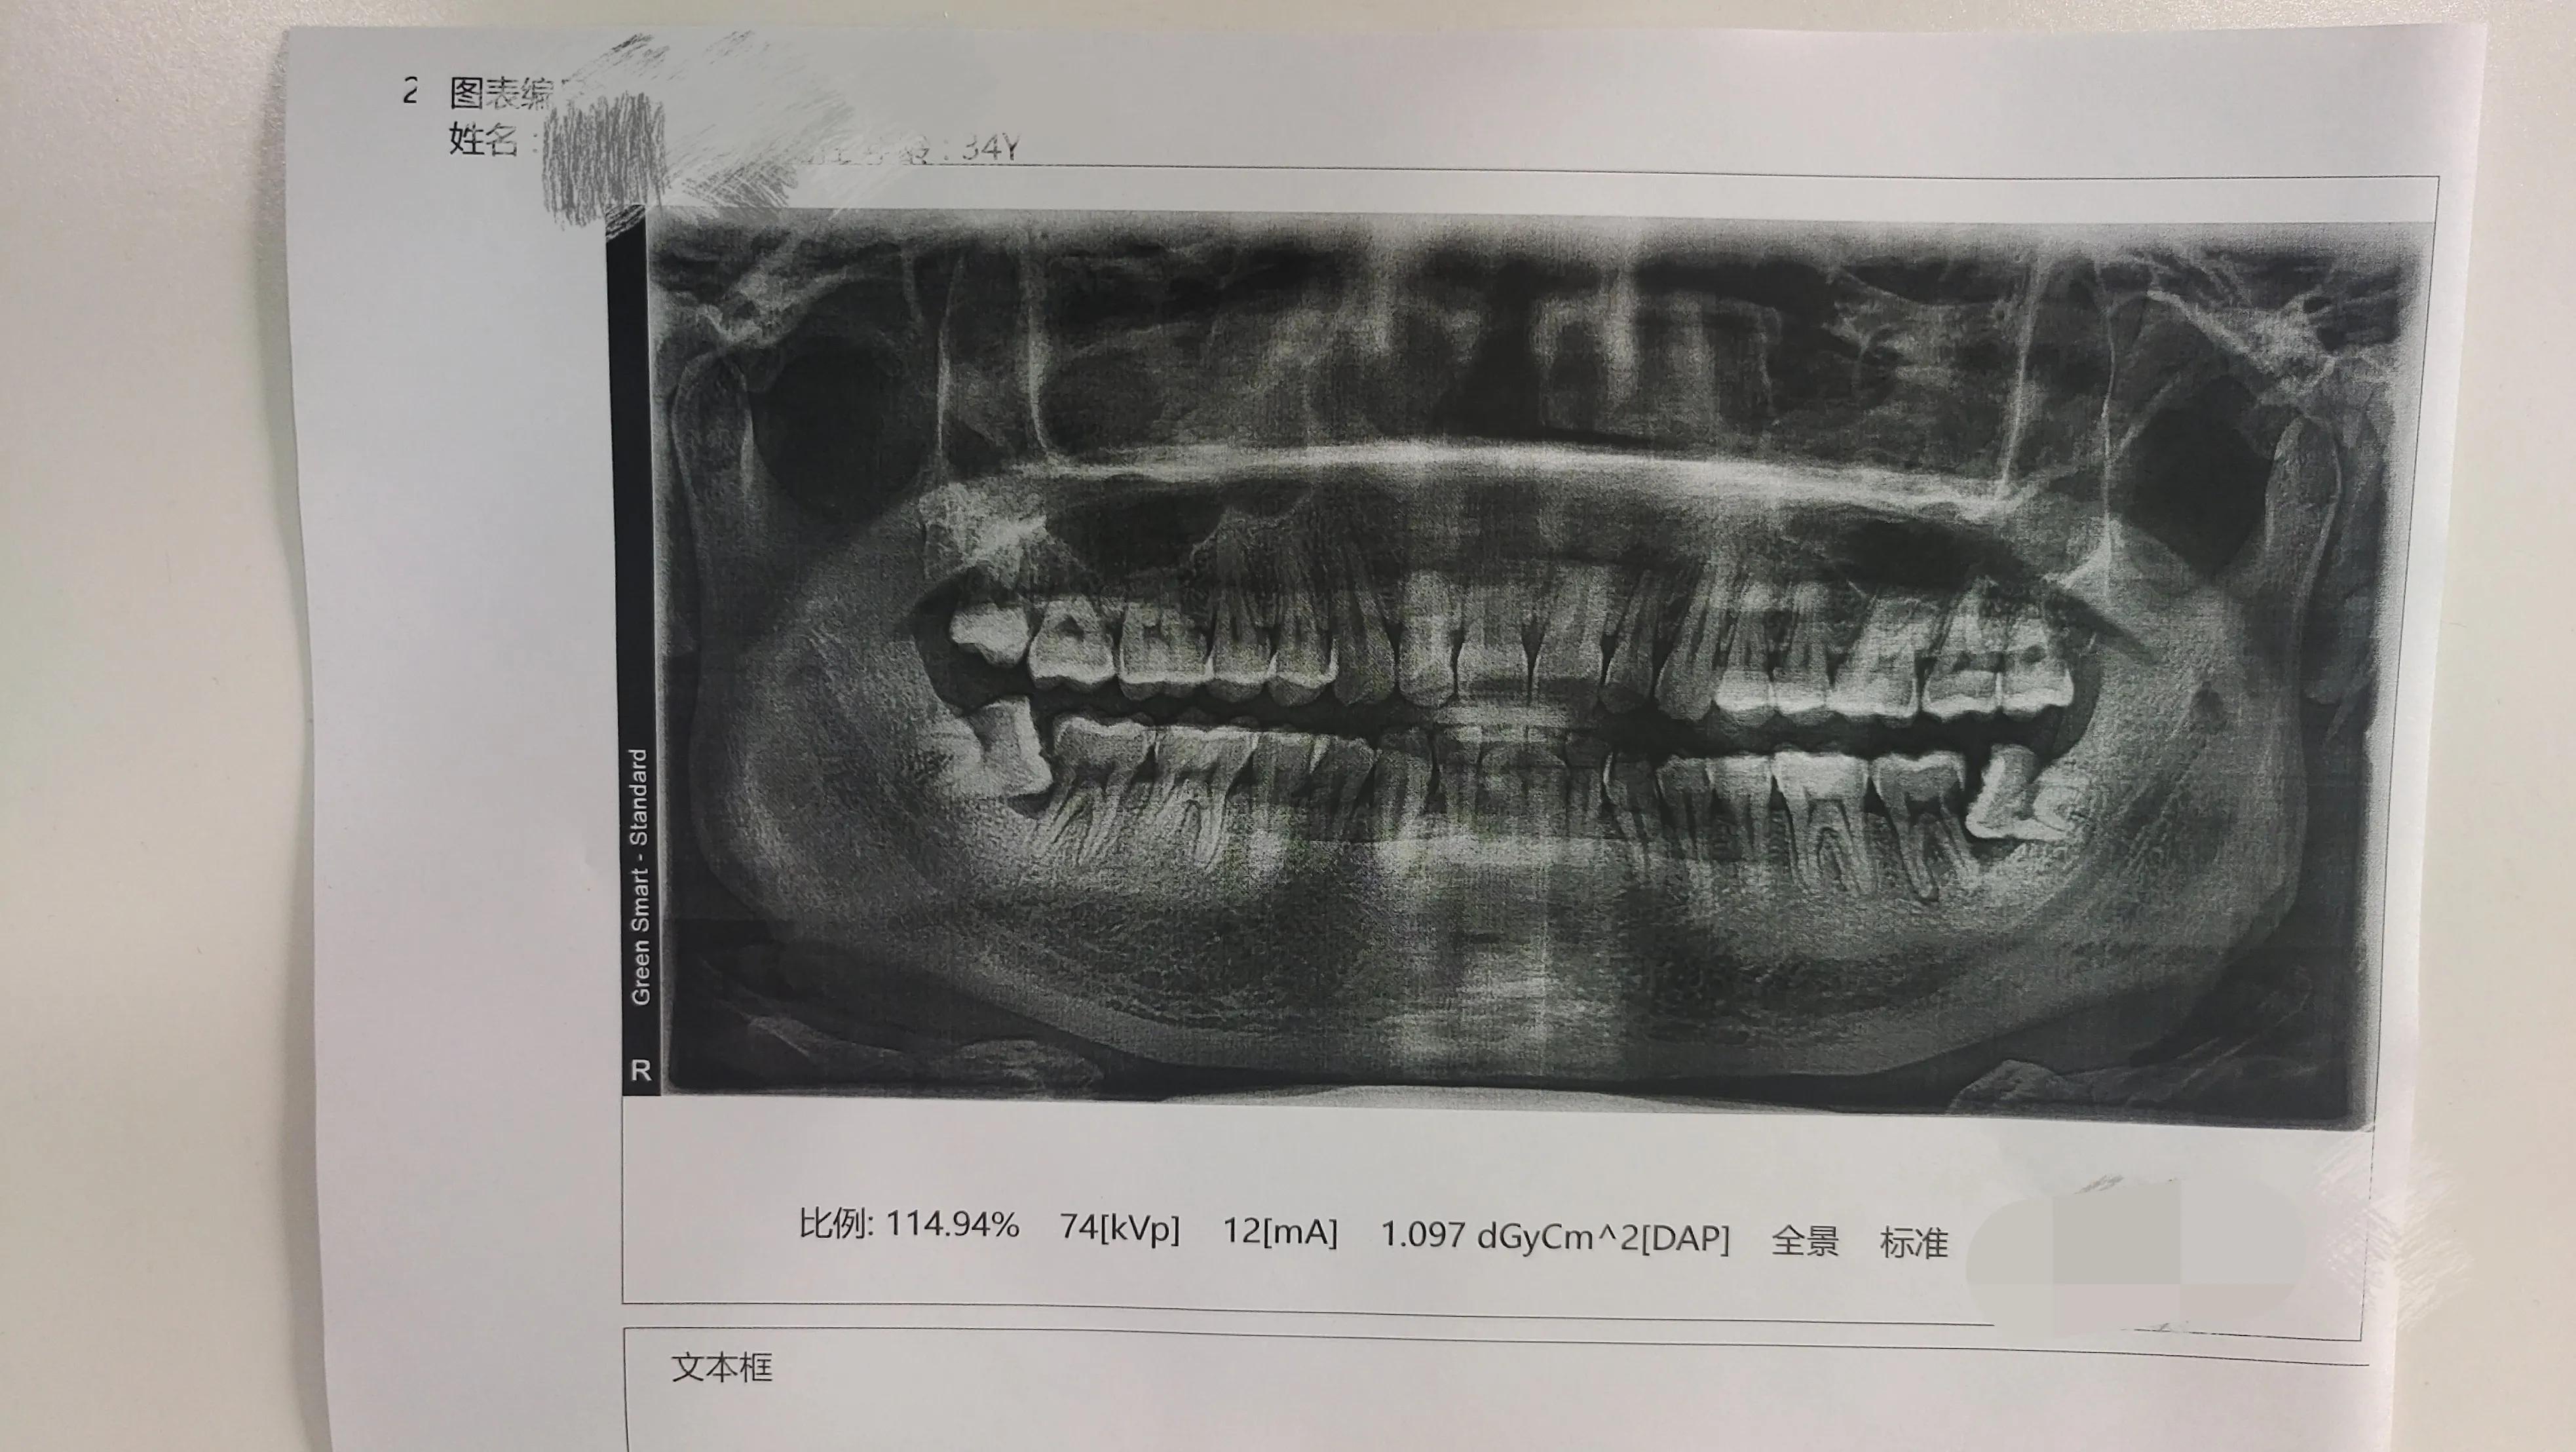

今年春节江苏这边疫情不严重,我就从镇江回无锡过年,刚到无锡没两天,左边后牙处突然开始隐隐的痛,以为是上火,过两天自己就会好了,就没管它,直到初二晚上和亲戚打了就算一夜的牌,从下半夜就开始疼痛难忍了,基本上就是一手捂脸一手打牌,是的。都说赌钱治百病,纯粹扯淡,最起码这牙疼是治不了。打到凌晨三点多钟实在受不了就结束了,然后在家翻箱倒柜的找止痛药,结果止痛药没有,就吃了两颗消炎药上床睡觉,把家人都吵醒了,以为半夜家中进贼。吃完躺在床上那是辗转难眠,疼的浑身冒汗,盼着天早点亮。好不容易熬到天亮去药店买了布洛芬吃下,没一会感觉就好多了,逐渐不疼了。十年前我这牙也疼过一次,嘴巴都不敢张大,那次去医院看了说是长智齿的原因,当时医生建议让我消炎不疼了过来拔掉,一听拔牙,吓得我脑门冒汗,我十来岁的时候邻居家就是私家牙科诊所,我可是亲眼目睹过拔牙的,一颗牙用那钳子在嘴里拔好多次,最后拔出来的那一下,嘴里的血一下子就溅出来了,吓得我连忙跑回家,待屋里半天没敢出门,以至于往后一听谁说拔牙的事就想起那场面后背发麻,现在突然听说医生要拔我的,那一秒钟惊的我是魂飞魄散,男人的面子促使我很快假装处于平静,医生说什么我嘴里都是应付好好好,心里其实早就想溜了,最后拿着医生开的处方单买了药就回家了,几天过后好了就没再去,一直到现在,中间就没再疼过。我本以为这次也一样,不疼就好了,没想到这才是起点,往后几天一直反反复复的疼,直到前两天回到镇江这边吃止痛药也没用了,才又去了市医院,挂完号到牙科一看,*靠我**,在我前面等候排队的二十来个,牙科是一个大间用一米多高的隔板分割成五六块,进去就能听到每块传出来的仪器马达声,脑子里想象着这个医生手里拿着钻子,那个医生手里拿着砂轮机。诚惶诚恐的好不容易等到自己,医生稍做检查问了几个问题后让我去拍个牙齿全景影片,就是下面的这张图片。

拿着片子给医生,医生第一句就是:“左边这颗智齿生长的顶坏隔壁牙齿,智齿要拔掉,坏牙要做根管治疗修补”。还说我这智齿有难度,不怎么好拔,要我明天上午过来,今天已经四点多来不及了。我说:“有没有不用拔牙的方案?能不能把智齿磨短一点”?医生坚定的回答:“必须拔,而且你要做好心里准备,过程可能是一个小时,也可能是两个小时,拔的时候有可能会敲的头不舒服”。尼玛,我感觉这医生应该转行到鬼屋里上班,他这要是自己的私人牙科,我估计这医生西北风都喝不到,病人要不被吓死,要不被吓跑,我是属于两者之间的,吓个半死跑了。出了医院心里想着医生会不会出于某种原因没给我讲其它治疗方案,于是我又重新找了个私人牙科咨询了一下,结果方案是一样的,只是讲的没之前的医生恐怖,但他不能给我拔,说我这牙需要两个人操作,他一人不好弄。我突然想起以前看过一篇文章说可以把牙齿分割开再拔,创伤风险小,就问了他这个方案,他说这个仪器他这没有,给我推荐了扬中市区这边一家有名气的私营牙科医院,那里应该会有。于是第二天上午开车带着老婆一起导航到了这个医院,进去了第一印象环境非常好,私营医院就是不一样,脑子里突然联想到莆田系医院,随即心里开始忐忑治疗费,来之前虽已抱着多花钱少受罪的想法,但还是怕相差太大,不过一番询问下来还挺惊讶的,比刚开始市医院医生预计的费用还少一点,跟我说是微创的,也不难拔,医生一句不难拔立马让我放松了很多,原本还在犹豫的我立马交费决定开拔,交完费直接由我的主治男医生过来带领我到楼上的房间,指示我躺在椅子上,随后医生叫进来一个助手,我掉头望过去,通过戴着口罩的剩余脸面,我断定是一个好看的小姐姐,只要口罩下面隐藏的不是猪嘴唇。医生大概给我看了一下牙齿,就开始动家伙了,本来还在前后左右到处瞄的眼睛看到装着麻药的针筒从我眼前划过的那一刻瞬间紧闭,多年未打过针的我都能感受到针筒伸进嘴里带来的寒意,扎进去时我顿时不由自主的发出了声音,不知是叫出来的还是哼出来的,好像扎了两三下,没一会就感觉左边嘴巴开始发麻,旁边的小姐姐来来去去的拿着一些东西过来,本想跟小姐姐聊两句的,奈何嘴巴麻的不灵活了,说了也是口齿不清,影响我的形象,就看看吧,还是不说了。医生过来试了试我嘴巴,感觉麻的差不多了说给我做坏牙的根管治疗,先打眼上药,他讲完我就立马闭上了眼,听到嘴里马达发出的嗡嗡声,脑子里在猜这是砂轮机在打磨还是钻头在打眼?突然间的疼痛让我肯定了此刻嘴里的是钻头,医生跟我说这颗坏牙暂时放进药就好了,以后还要来个两三次。趁医生停下的空间我坐起吐了吐嘴里,小姐姐给我递了一杯漱口水,漱完接着躺下,准备迎接我的终极一战,刚刚放缓的心情立马又提到了嗓子眼,一阵嘴巴里断断续续的嗡嗡声后安静了下来,我口齿不清的问道:“好了吗”?医生来了一句:“还没拔了,哪有这么快”。我心顿时拔凉拔凉的,NND,我这是白吓这么长时间了。坐起来再吐了吐嘴里带血的口水,感觉嘴巴张的好累,闭上嘴都是一种享受,同样小姐姐又递来一杯水,只是我不再想跟她说话了,接过来漱完就躺下。过了一小会,医生转过了身,我看到他右手中拿着一把钳子,形状未曾见过的钳子,不,不是一把,左手托盘里还有其它器械,里面还有钳子,放在里面显得那么突兀,我赶紧闭上眼,心里不是紧张,是恐惧,医生让我张开嘴巴,还要我张大点,我说我嘴巴张的太累了,医生开玩笑说他手也累,我心里顿时有上万只草泥马奔过,原来你刚才也是在休息,是在等着恢复元气,准备放大招了吗?没等我再多想,已经感受到钳子夹住了我的牙齿,在嘴里咔擦咔擦的夹来夹去的,疼虽然不疼,但吓人的程度一点不亚于市医院的那位牙科医生,真的是“伤害性不高,*辱侮**性极大”,紧闭的眼睛都能感受到眼角是湿的,不知是吓得还是长时间紧闭双眼导致的,医生说已经夹出来一小块了,我心想“他这拔牙是这样拔的?微创就是不一样,不用敲敲打打的,真好,还有一半应该也快了”。没想到我想多了,医生说完这话接下来的动作就不按套路了,刚才停下说话时我睁开眼看到他是坐着的,说完这话重新拿了一把钳子突然站起来了,他这姿势的转变立马颠覆了我刚才自以为是的想法,我不知道他有没有感受到我看向他时眼睛里流露出的恐惧、哀求、绝望。他站了站对我说:“现在开始拔了”。窝尼玛,原来前面的嗡嗡的”“咔擦咔擦的”只是前戏,高潮还在后面呢!闭上眼,张开嘴,心里想着:来吧,尽情的*躏蹂**我吧。他倒也没让我失望,不知道是谁的手摁着我的下巴,他手里的钳子夹住我的牙齿就往上拉,被摁着我都感觉头带着身子逐渐脱离躺椅,嘴里不自觉的随着他反复拉的动作嗯啊嗯啊的发出声响,钳子还夹在我牙上了他还问我疼吗?我也不好说话,就“嗯”了一声,他说很疼的话就再打支麻药,我听他这么一说赶忙模糊不清的回了一句“可承受范围内”,说实话,不是很疼,但是极度紧张害怕,感觉嘴巴上下之间是被千斤顶顶住了,想缩小一点都不可能,特别累,夹着牙齿的钳子使力绷住劲地往外拉,我脑子里一直在想想医生的动作是什么样的?一会想象他像在拔河比赛,助手在旁边给他加油;一会想象他两腿前后拉开步伐,一手抵着我的下巴,一手往外拉,就像手里在拔着一块带钉子的木板,不是用脚踩着木板往上拔的那种,就这样一直不停的想象。他拔一会停一下,停一下我起来吐一下,反反复复好几次,每次吐口水就感觉后面的牙逐渐凸起来,直到最后很疼的一下拔掉了,听到医生说拔了的那一刻,身体感觉一下子软了下来,就像泄了气的气球。拔完心情立马好了起来,刚想坐起来同医生和小姐姐调侃两句,医生一团棉花球塞进我的嘴里道:“别动,等下伤口还要缝两针”。突然脑袋懵懵的,我这不是微创吗?还要缝针?医生你是迪士尼乐园里的小丑吗?总让我不定时的有惊奇!一番操作下来,总算结束可以起来了,嘴里的棉花要我咬半小时,得了,这下彻底无语了,那就闪人吧,刚要走,医生叫住我,说要跟你说一下注意事项,我嘴巴不好说话,就把门外的老婆叫进来,让医生跟她讲了,我自己去了洗手间,照着镜子看到满嘴血迹,洗完出门就带着老婆准备回家了。出医院门口已经中午了,本想在外面吃午饭的,老婆给我说医生叮嘱了要我两个小时后才能吃饭,算了,那还是回家吧。回到家老婆一会就做好了饭,我就坐在客厅看着老婆儿子吃,早饭本就没吃,早就饿的咕咕叫,看着他们吃饭简直度分如时,他们吃完了我就数着时间等自己的开饭时间,好不容易熬过两个小时去厨房盛饭,结果老婆给我端了碗面条,我说:“你们中午吃的不是米饭吗?怎么还有面条的”?老婆说:“医生让你吃清淡的,所以我给你专门煮了面条”。我知道这婆娘是让我光吃饭不吃菜了,我端着面条坐回餐桌上,望着他们吃剩下的我最爱的鸡脚,趁老婆没过来夹起一个就吃了起来,结果还没吃完就被老婆看到了,赶紧给老婆*脑洗**辩解:“你看,我拔的是左边最里面的智齿,又不影响我正常吃饭,人家做手术动刀流血过后都是大鱼大肉的补,我为什么就只能喝清粥吃烂面?医生那是习惯性的医嘱,我这个没事的”。经过我的唇枪舌剑,我不但吃上了鸡脚,还吃上了鱼,结果就是晚上半边脸肿的不想张嘴,自愿喝起了清粥……